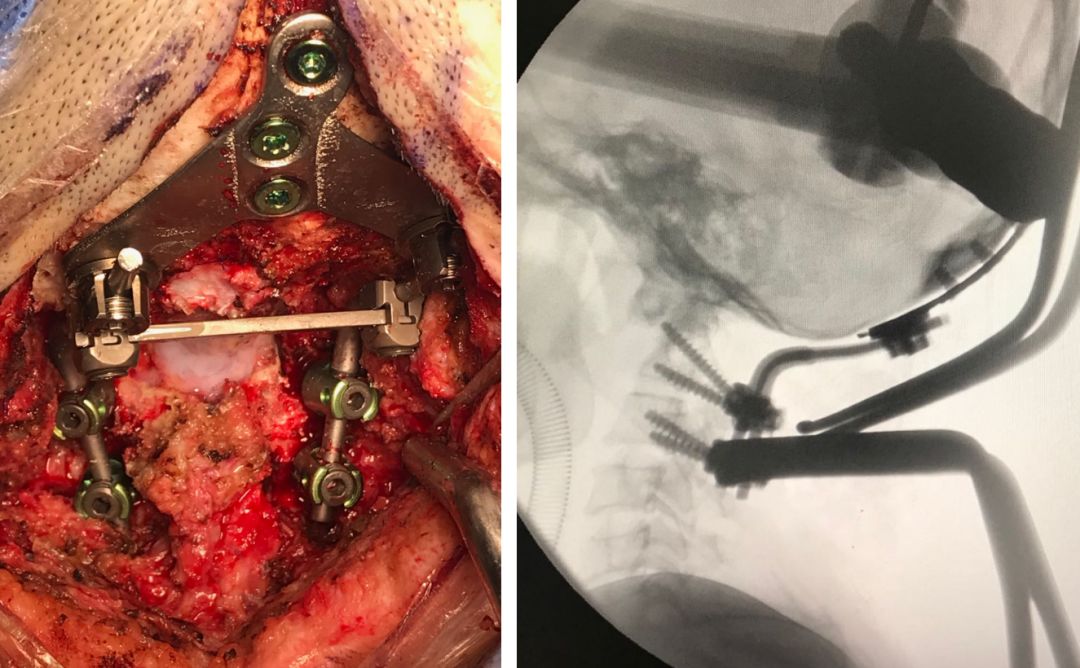

术中对双侧侧方关节做松解,而左侧优势侧椎动脉,术中需做动脉移位才能暴露畸形的C0和C2。

对右侧侧方关节做关节成型术,去除C2部分上关节突,以暴露绞索的C0和C3侧块。

侧方关节松解后,在关节间植入松质骨促进骨融合,并行枕颈融合术。行双侧C2椎弓根,C3侧块螺钉。